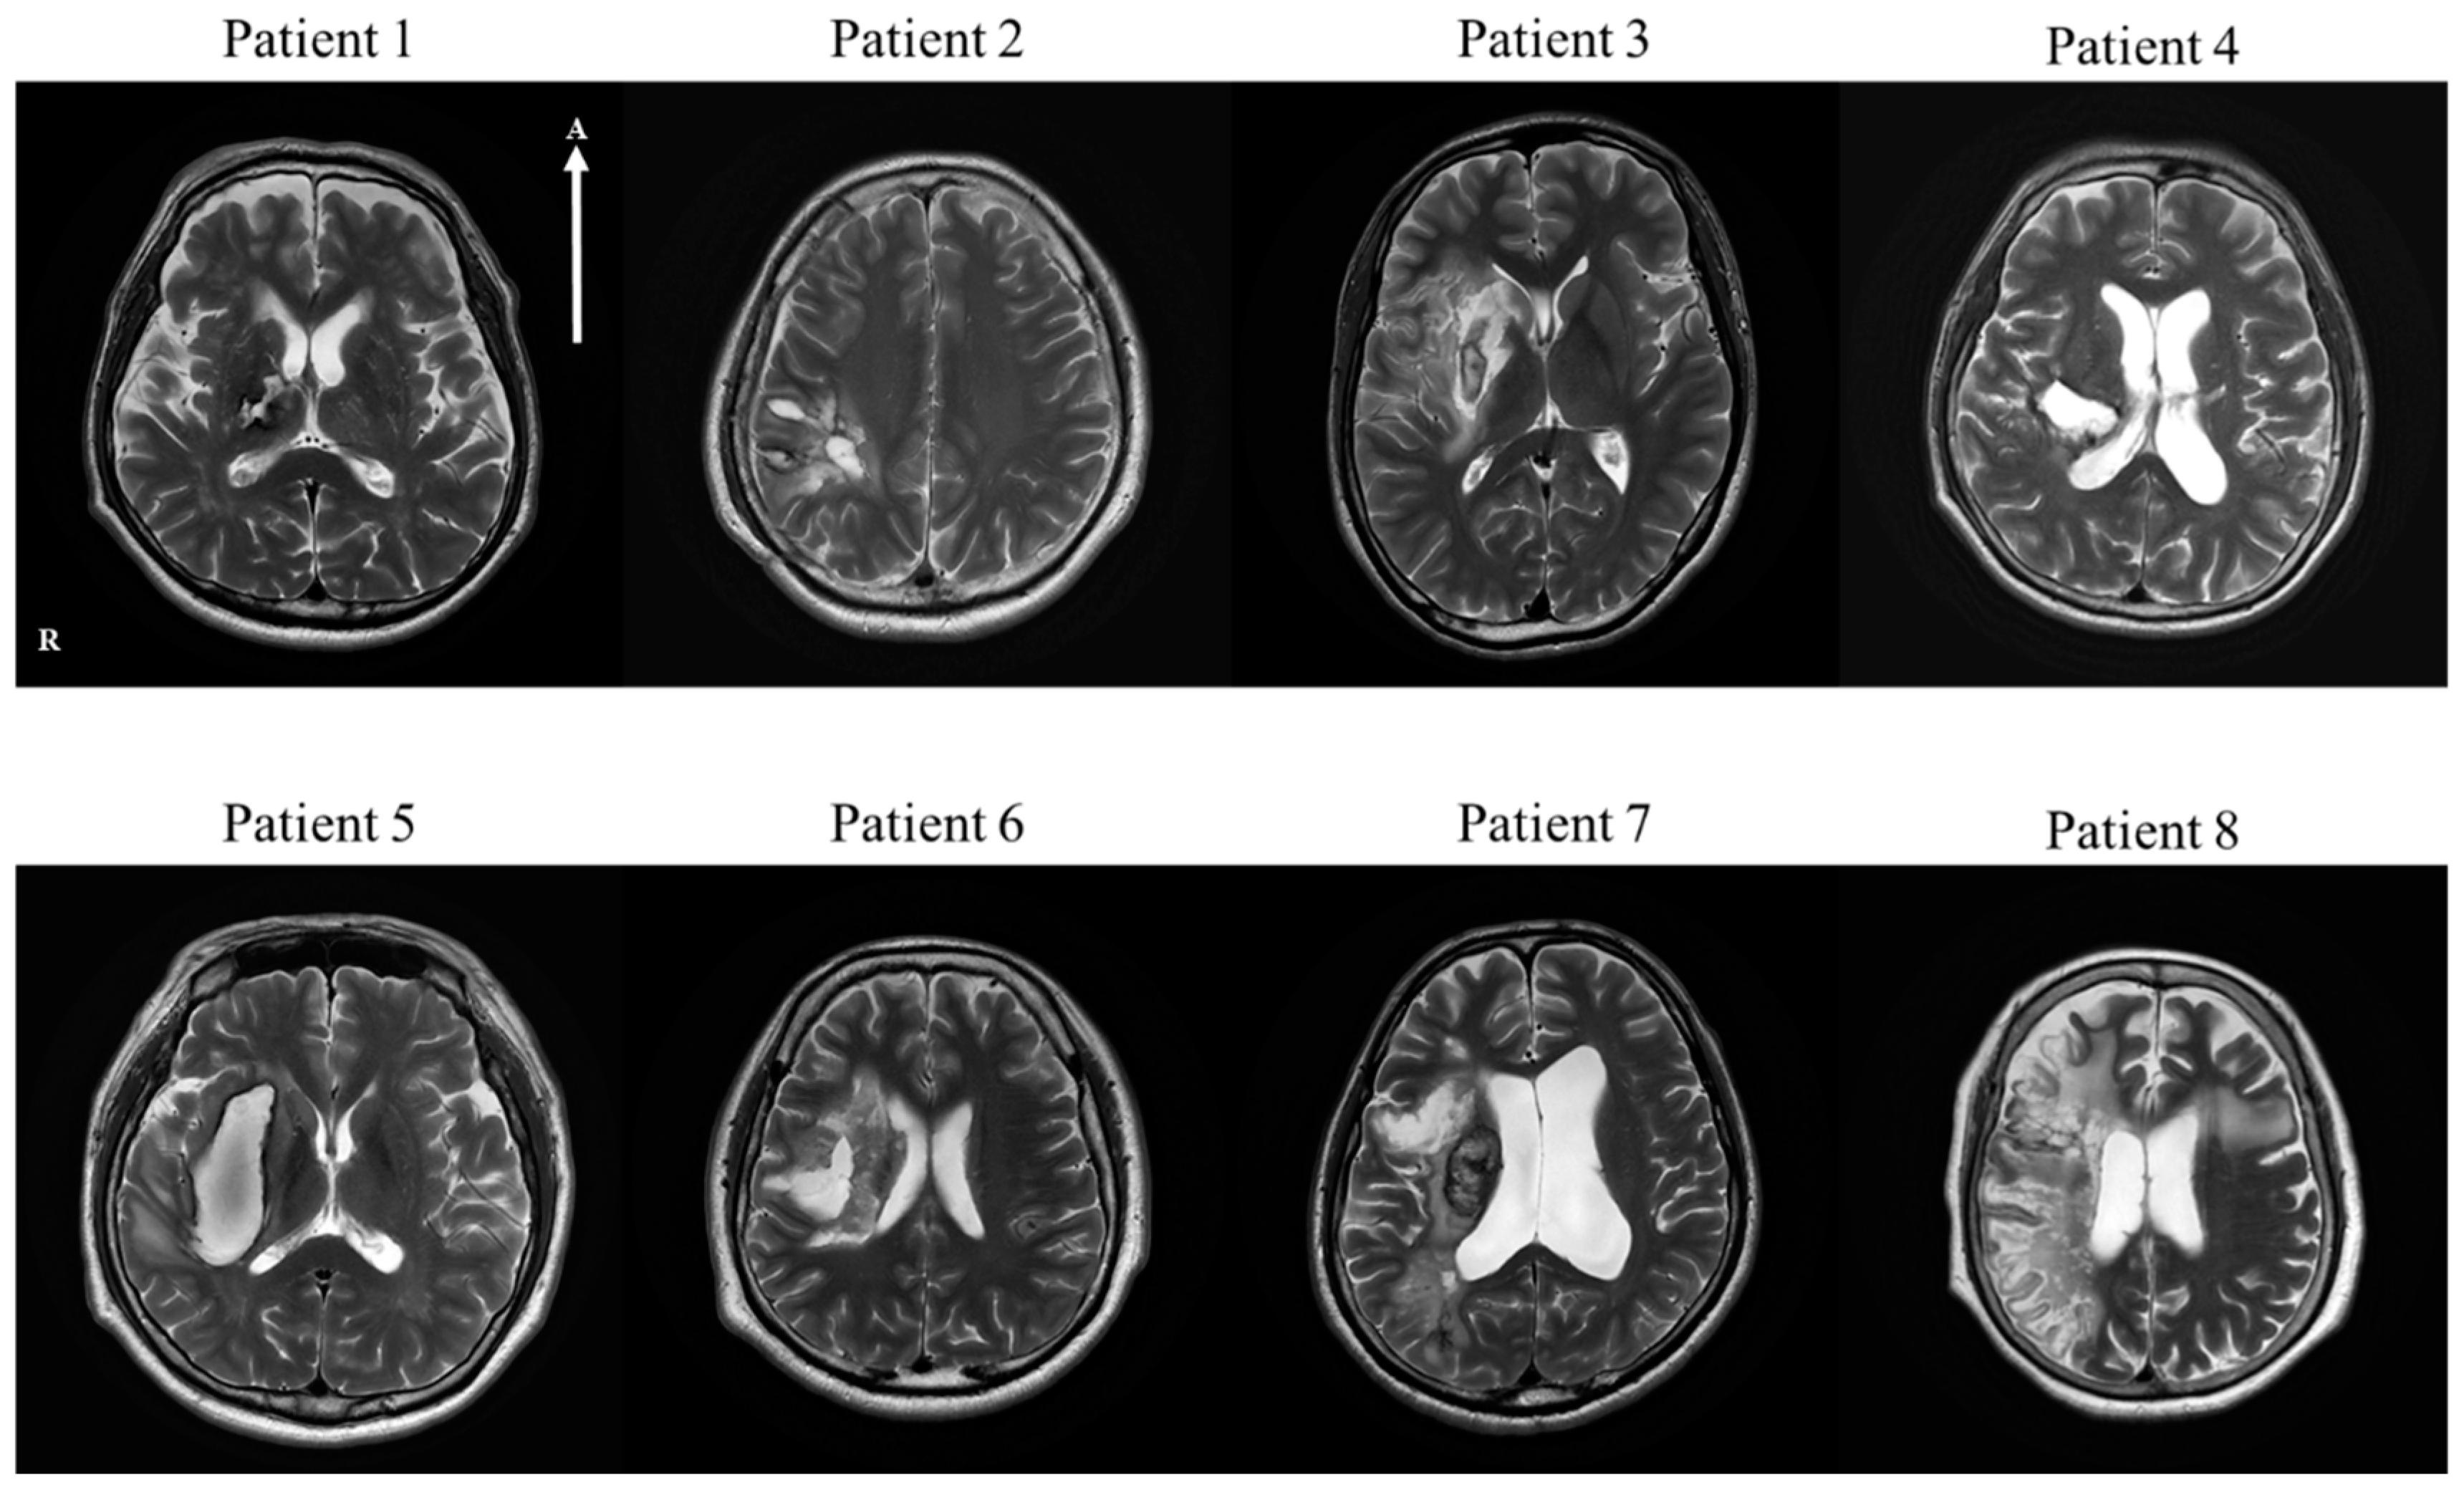

| No | Age | Sex | Lesion | Type | MMSE | Medical History | Operation | Medication for Stroke |

|---|---|---|---|---|---|---|---|---|

| Patient 1 | 68 | M | Thalamus and posterior limb of internal capsule, right | H | 23 | HTN | Craniotomy | |

| Patient 2 | 37 | M | Parietal lobe, right | H | 30 | Craniectomy and Cranioplasty | ||

| Patient 3 | 23 | M | Frontal lobe, insular cortex and basal ganglia, right | I | 28 | cilotazol, atovastatin | ||

| Patient 4 | 47 | M | Basal ganglia, frontoparietal lobe, right | H | 17 | HTN | Conservative treatment | |

| Patient 5 | 61 | M | Basal ganglia, right | H | 26 | HTN, MI | Conservative treatment | |

| Patient 6 | 48 | M | Basal ganglia, right | H | 28 | Craniotomy | ||

| Patient 7 | 67 | M | Frontal, parietal, temporal lobe and insula, right | I | 26 | Thrombectomy | aspirin, atorvastatin | |

| Patient 8 | 69 | F | Basal ganglia fronto-temporal lobe, right | I | 21 | AF | Thrombectomy | micronized rivaroxaban, atorvastatin |